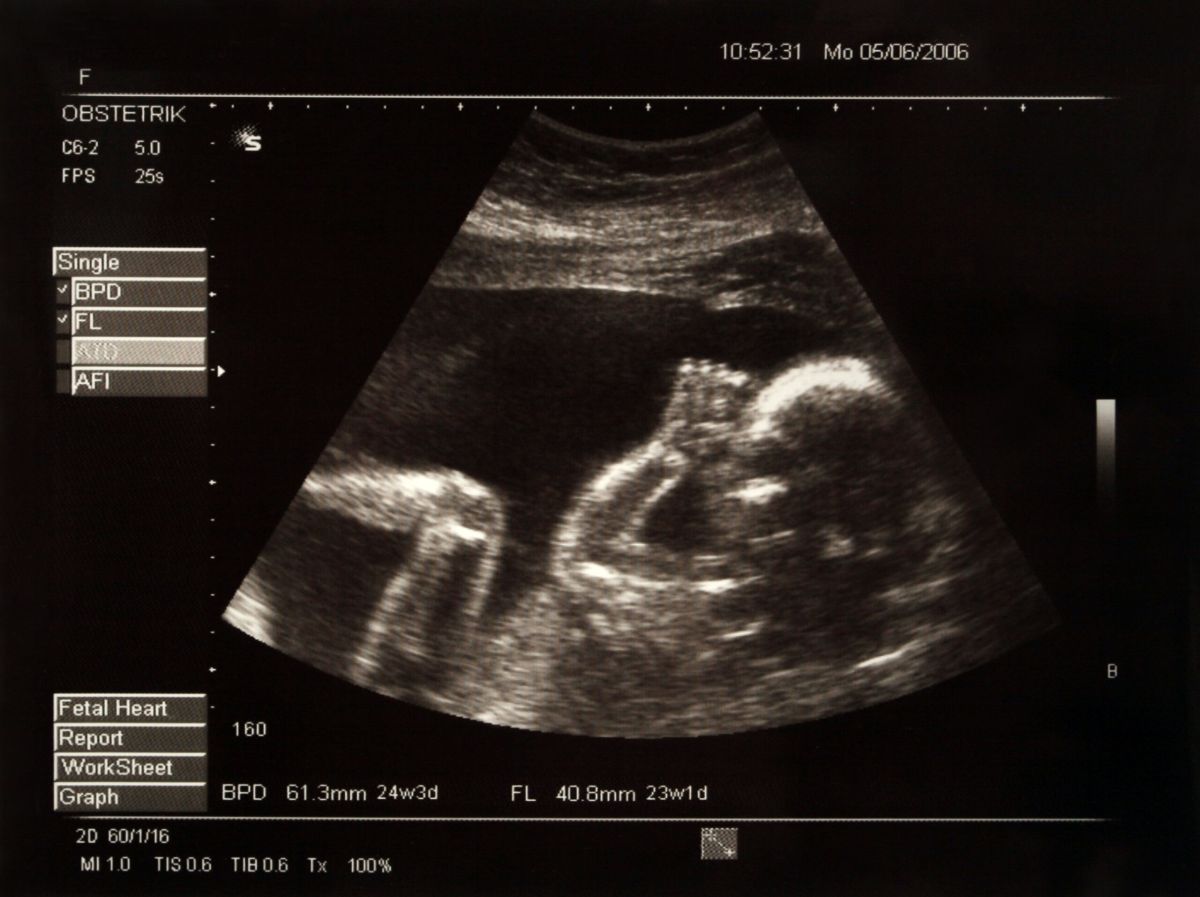

Picture of a baby in the belly of her mother

L’anomalie a été découverte lors d’une séance d’ultrasons à la 30e semaine de grossesse. Les parents ont alors décidé de participer à un essai clinique inédit mené conjointement par le Brigham and Women’s Hospital et le Boston Children’s Hospital. Attendre la naissance pour intervenir aurait pu aggraver la malformation et entraîner de graves complications cérébrales. En effet, selon le radiologue Darren Orbach de l’hôpital pour enfants de Boston, 40% des enfants atteints de cette maladie décèdent peu après leur naissance.

L’intervention a été réalisée avec succès en assurant une position optimale du fœtus dans l’utérus de la mère. Des injections ont été administrées pour maintenir l’enfant en place et soulager la douleur. Un cathéter a été utilisé pour ralentir le flux sanguin et réduire la pression. Les chirurgiens ont été guidés par des ultrasons tout au long de l’opération. La petite fille est finalement née deux jours plus tard.